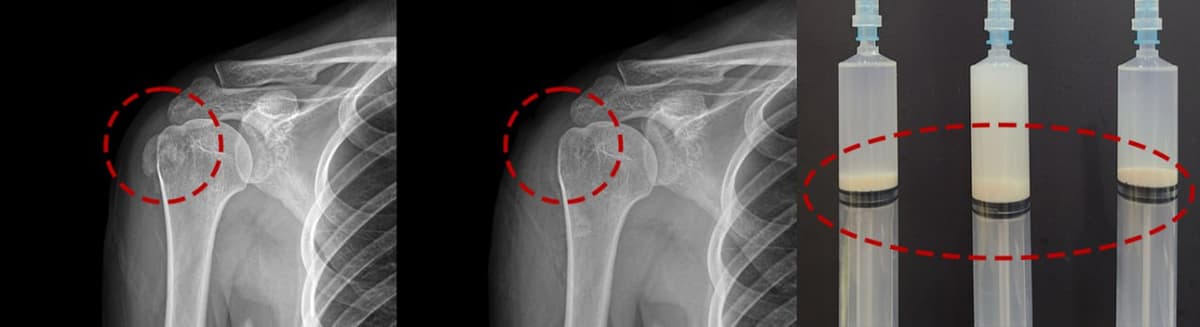

施術前後のX線比較

硬化した石灰も1回のセッションで完全除去。実際の患者様のX線画像です。

X線で肩腱に白い石灰の塊がはっきりと確認できます。

1回の破砕吸引術で石灰が完全に除去されました。